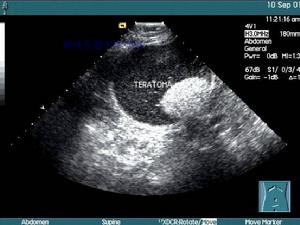

B超檢查按現代的分類,WHO(1993,2000)將腫瘤分為3個亞型:①成熟性;②未成熟性;③畸胎瘤惡變